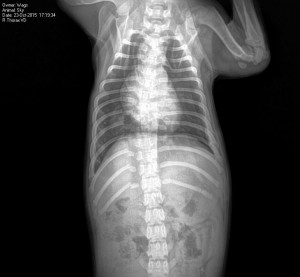

In a horrible twist of fate, Sky somehow has had to avoid euthanasia at the same shelter in North Carolina twice. First she was adopted from the shelter directly to a forever home, which turned out to be a

temporary hell, where she suffered broken ribs, a broken leg and fell ill with parvovirus.

nd another injured dog the same night. It was recommended that Sky be euthanized due to all the pain associated with her injuries and the parvovirus that rendered her too weak for surgery. Despite all of this, Sky continued to wag her tail!

Instead, WAGS fought harder to keep her alive and took her to an emergency vet in North Carolina where she was immediately treated for parvo. Things were looking good the next week and the vet opted to try to save her leg and put it in a splint.